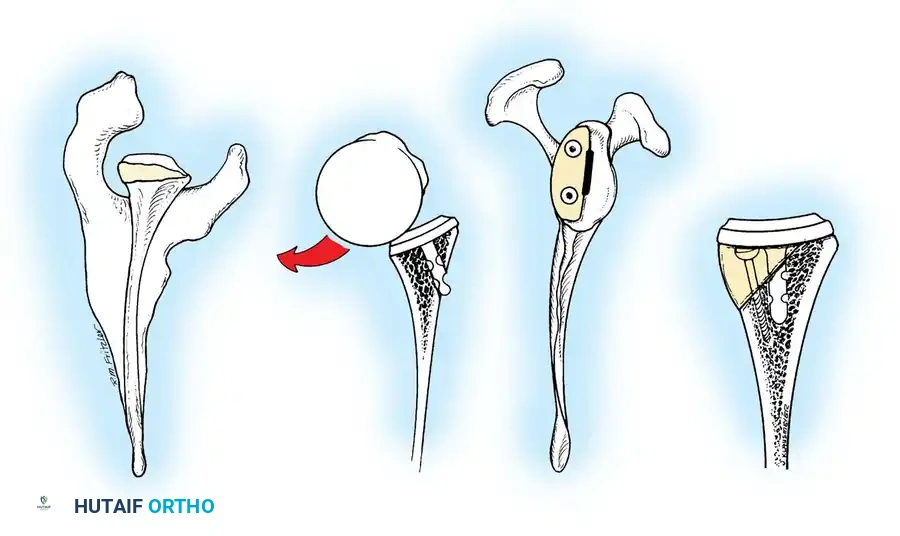

Reverse Total Shoulder Arthroplasty (rTSA)

The rTSA fundamentally alters shoulder biomechanics. By medializing and distalizing the center of rotation, it increases the deltoid moment arm and recruits more anterior and posterior deltoid fibers for elevation, bypassing the need for a functional rotator cuff.

Surgical Nuances for rTSA:

* Glenoid Baseplate: Must be positioned inferiorly on the glenoid to avoid scapular notching. A slight inferior tilt (10 degrees) is often utilized.

* Glenosphere: Typically 36 mm or 42 mm. Larger spheres increase stability and range of motion but may increase the risk of notching.

* Humeral Stem: Often placed in 0 to 20 degrees of retroversion.

Clinical Pearl: Tensioning is the most critical step in rTSA. The joint should be stable in all planes. If the joint dislocates easily, a thicker polyethylene insert or a larger glenosphere is required. However, over-tensioning can lead to acromial stress fractures or brachial plexopathy.